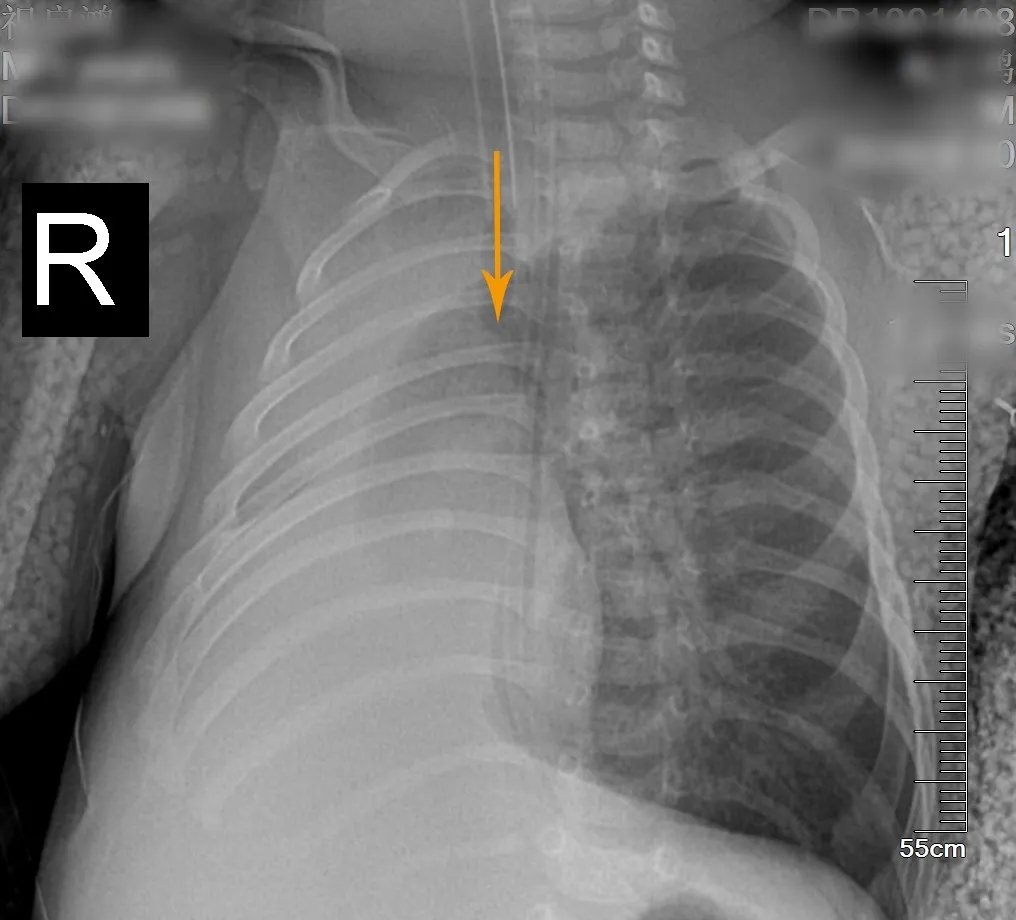

转入我院后,小华出现呼吸困难加重、紫绀,医生立即予气管插管、呼吸机辅助呼吸。同时结合床边DR与外院胸部CT,发现小华右肺不张,气管有高密度增高影,高度怀疑其主气管内有异物且非家属说的可能是米糊类食物,但小华家属否认喂食过米糊或牛奶以外的食物。

(左图为术前DR胸片,右肺完全肺不张;右图为术后DR胸片,右肺完全复张)